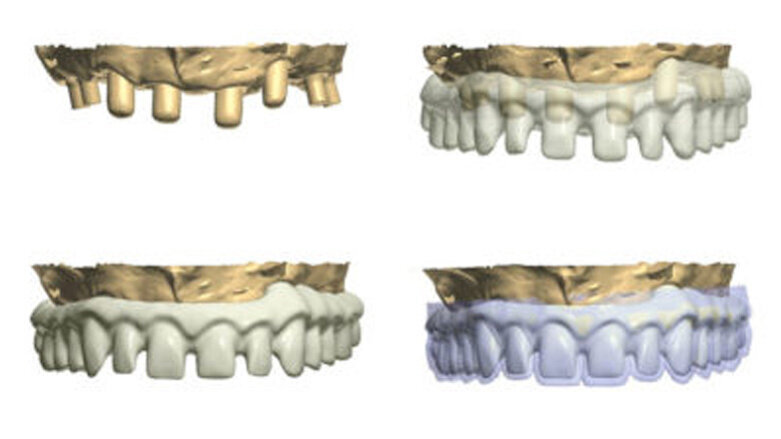

Fig. 1: A virtual image of a scanned model with abutments and telescopic crowns.

Fig. 2: Design of the construction with the transparency mode on.

Fig. 3: Ready-made construction on a virtual model.

Fig. 4: Scan of the temporary prosthesis (blue color) visible against the design of the construction.

In order to prepare the bridge, a model was scanned and transferred onto a computer using software to design the bar (Fig. 1). The bar was designed by using special software in such a way that the whole design was transparent in the first phase so that the location of abutments and the position of the telescopic abutments at the frontal section could be visible (Fig. 2).

Having planned the proper shape and location of pillars for the porcelain crowns, the transparency was switched off (Fig. 3).

The next phase involved the planning of the size and shape of the final teeth, which, as porcelain crowns, will be glued onto the construction (Fig. 4). For that purpose, it is very helpful if on the design of the bar, a scan of the patient's temporary model prosthesis can be planted.

The patient must first approve the wax-up, in aesthetical and functional terms (Fig. 4). A computer programme for designing such constructions provides us with the possibility of viewing and designing the bar from all angles. Figures 5 to 9 show some exemplary prints of the views visible from the occlusal surface. Having finished the designing process, the bar should be visually inspected from the intragingival side (Fig. 10).